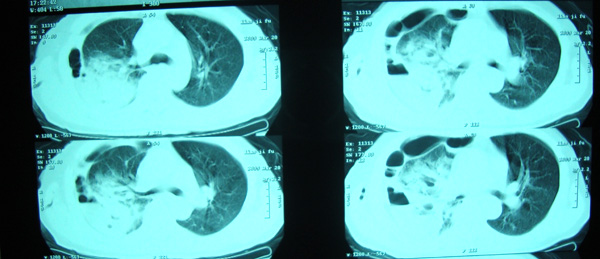

20日院外ct检查,片示于后.

院外ct说排除膈下脓肿,请大家发表意见.

1)考虑右肺感染性病变(化脓性肺炎或肺脓肿可能)。2)右侧液(脓)气胸,部分包裹。

考虑1、右膈下脓肿并肺脓肿,2、右侧液气胸

右侧膈肌抬高明显,胸腔内无明显积液,表现为胸膜反应,肝脏周围大量积液,并见多个液气平面。右下肺不均匀密度增高影。结合临床考虑右侧膈下脓肿并腹腔内积液、右下肺并发感染及胸膜反应,节段性肺不张不除外。

右肺下叶见大片状病灶,密度不均,其内见透光区。沿右侧胸壁见多发含气腔,其间可见间隔,其内部分可见液平。膈肌下未见异常(纵隔窗窗位太低)。应该是典型的化脓性肺炎合并脓胸。

右隔下积脓并右侧肺脓肿;右侧液气胸